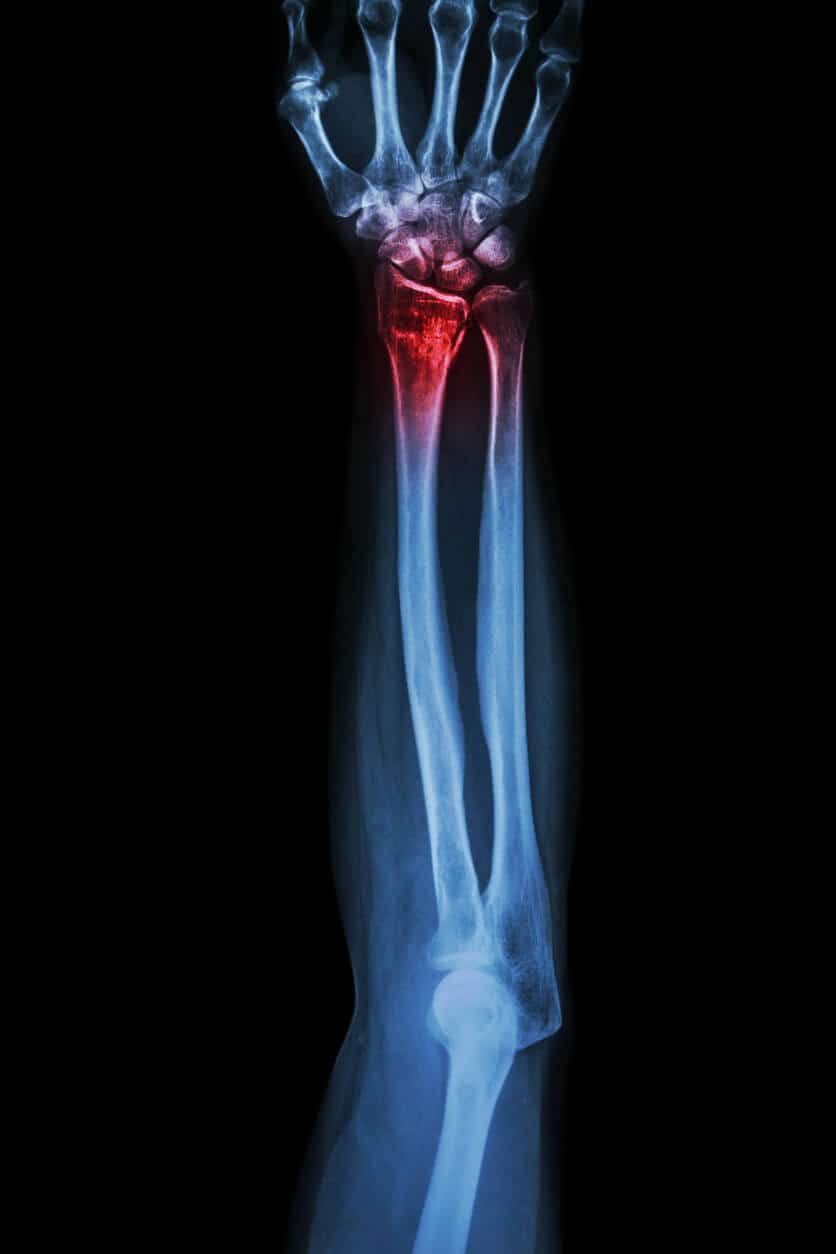

Can Urgent Care X-Ray Your Suspected Fracture?

In short: Urgent care centers are equipped to perform X-rays for diagnosing suspected fractures. Prompt diagnosis helps prevent complications and guides effective initial treatment. A crucial follow-up with a specialist is needed after your urgent care visit. If you’ve ever experienced a sudden injury — whether from a fall, a sports mishap, or an accident [...]